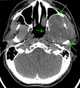

Mandibular schwannoma